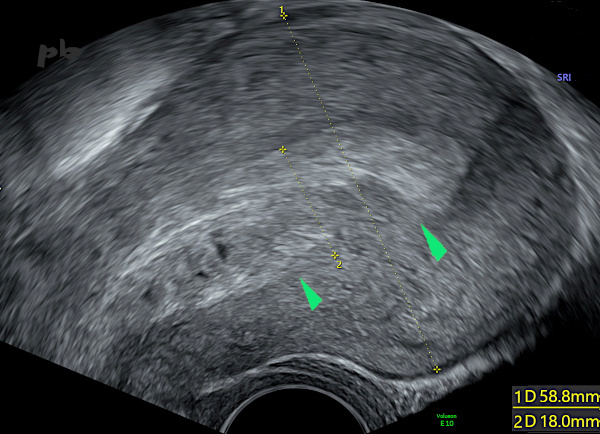

4 – Résidus trophoblastiques

Echographie – Coupe sagittale.

Muqueuse et cavité utérine très épaissies et hétérogènes (entre les croix 18 mm).

Entre les 2 marqueurs (►), l’interface endomètre – myomètre disparait.